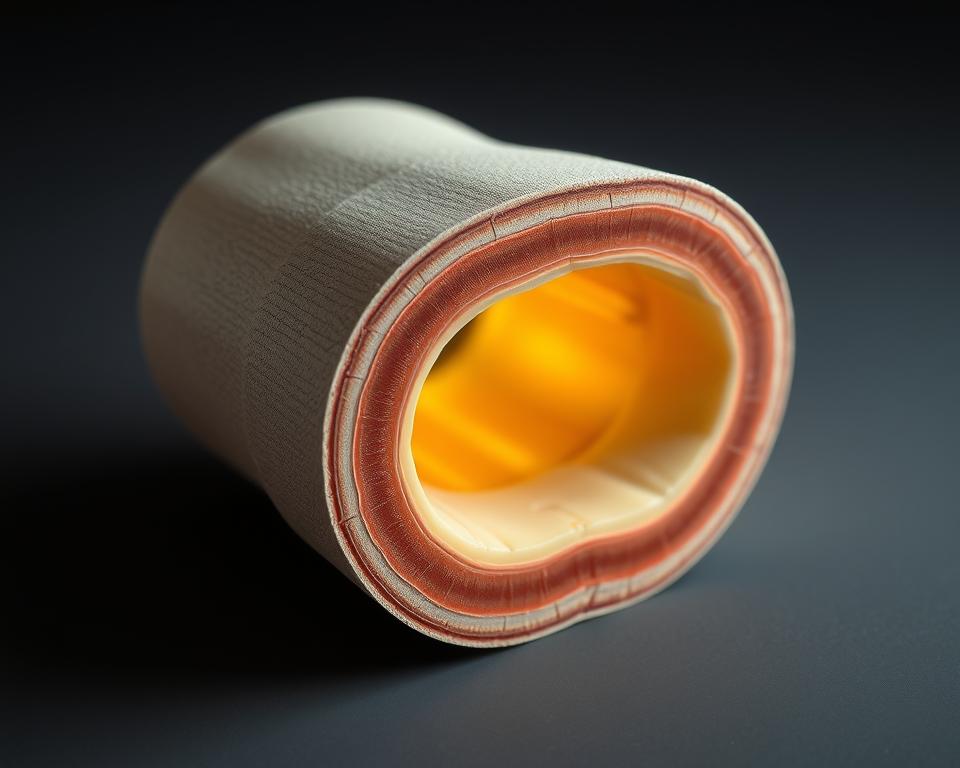

Budowa: błona maziowa i warstwa włóknista

Wewnętrzna część składa się z delikatnej błony maziowej. Ta żywa fabryka produkuje lepką maź, która działa jak naturalny smar – zmniejsza tarcie podczas ruchu i dostarcza składniki odżywcze do chrząstki.

Zewnętrzna warstwa to gęsta sieć włókien kolagenowych. Układają się one w specyficzne wzory, które decydują o stabilności stawu. W kolanie tworzą mocne pasma, w palcach – bardziej elastyczną siatkę.

Błona maziowa pełni podwójną rolę. Jej gęsta sieć naczyń krwionośnych działa jak filtr – kontroluje przepływ substancji między krwią a płynem stawowym. Jednocześnie produkuje białka chroniące przed infekcjami.

Warstwa włóknista przypomina inteligentny gorset. W spoczynku utrzymuje luźną strukturę, pozwalając na swobodny ruch. Przy nagłym skręceniu natychmiast napina się, blokując niebezpieczne przemieszczenia kości.